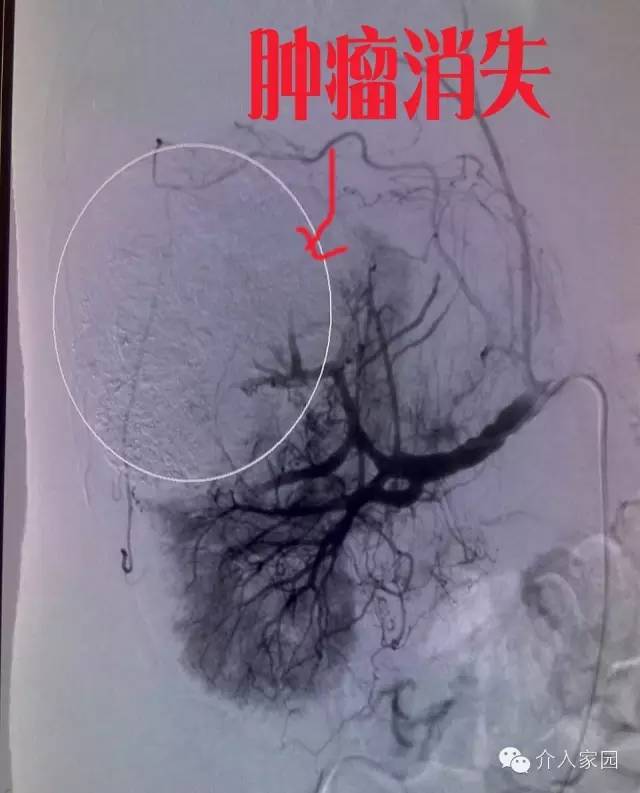

肺癌,我國最常見的腫瘤,發(fā)病率居腫瘤之首,它也會導致出血,很多病人就是因為大出血而死亡的??纯创髴c油田總醫(yī)院介入科提供的一個病例。右肺癌患者,伴咯血。如下圖,我們可以清楚地看到那一團肺癌腫塊。

這個是把腫瘤堵塞后表現(xiàn),我們可以看到,整個腫瘤消失,不再有血液營養(yǎng)供應了。所以這個患者不光止住了咯血,肺癌在失去血供營養(yǎng)后,也萎縮變小。